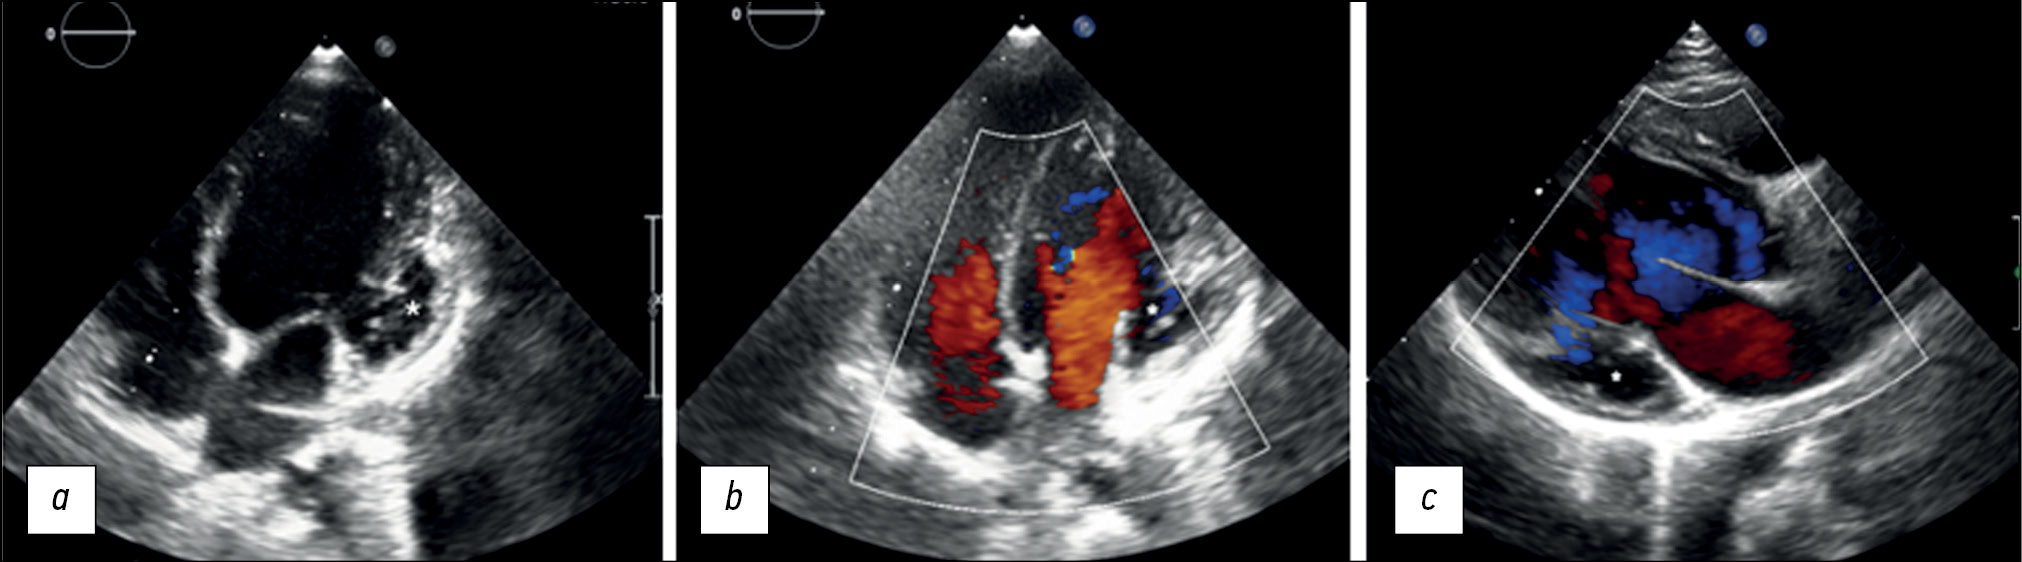

According to EchoCG and CMR, the patient has a noncompact left ventricular myocardium and aneurysm. Given the findings, it was decided to have a coronary angiography to assess the coronary vessels and exclude coronary artery anomalies. Coronary angiography showed no evidence of coronary artery abnormalities (Figure 4a and b).

Fig. 4. Coronary angiography of a 6-year-old patient with myocardial non-compaction and left ventricular aneurysm. The study was performed using a 4 Fr sheath and two 5 Fr catheters. a, b - no changes were detected in the coronary arteries; the left type of coronary blood supply is determined. RCA—right coronary artery; LAD—left anterior descending artery; Cx - circumflex artery; D1 - diagonal artery; RV branch - branch of the right coronary artery; AI is an intermediate branch.